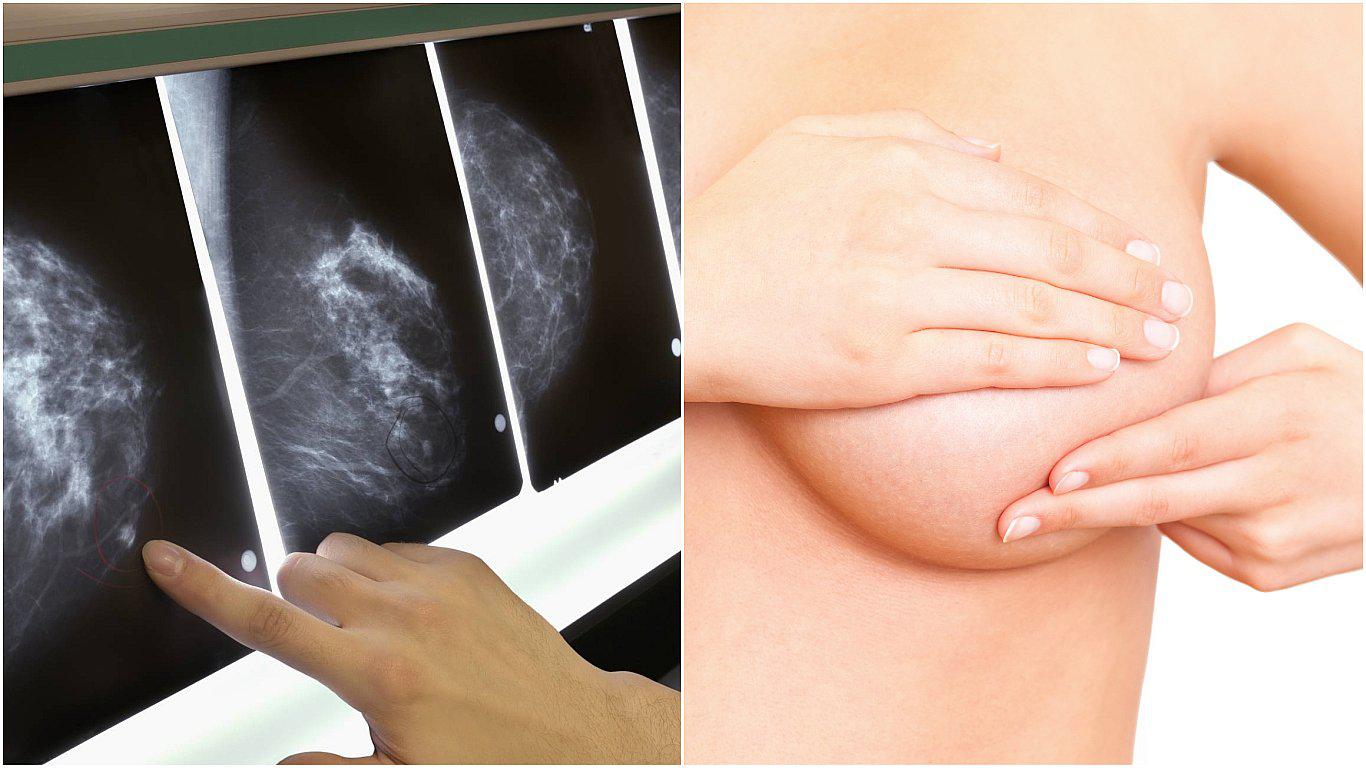

Un tratamiento de inmunoterapia con linfocitos T ha logrado, por primera vez, eliminar por completo las células cancerígenas de una única paciente con cáncer de mama, según publicó recientemente la revista científica Nature Medicine.

Así, una mujer de 49 años es la primera persona con cáncer de mama avanzado y metástasis en otros órganos que ha visto desaparecer todos sus tumores gracias a la inmunoterapia. Resulta que estos nuevos tratamientos, como la inmunoterapia, que adiestran al sistema inmune del paciente para que aprenda a reconocer y aniquilar las células del cáncer; funcionan sobre todo en tumores que acumulan muchas mutaciones genéticas en poco tiempo, como el melanoma y los tumores de pulmón causados por el tabaco.

La paciente, identificada solo con un el número 4136 para preservar su identidad, sufría un cáncer de mama avanzado que no respondía a ninguna terapia convencional a base de quimioterapia o tratamientos hormonales. Dentro de un ensayo clínico con pacientes con metástasis, los médicos del departamento de cirugía del Instituto Nacional del Cáncer de Estados Unidos analizaron muestras de sus tumores y extrajeron de ellos linfocitos, células del sistema inmune. Los investigadores secuenciaron el genoma completo del tumor e identificaron las 62 mutaciones que había acumulado.Cada uno de estos errores en el ADN pueden generar fragmentos de proteínas conocidas como neoantígenos. Los médicos analizaron los linfocitos de la paciente en cultivos celulares, seleccionaron los que eran capaces de identificar cuatro de esas moléculas mutadas y dejaron que se multiplicaran en cultivos de laboratorio.

Finalmente, la paciente recibió una sola inyección que contenía miles de millones de linfocitos seleccionados, un equipo inmunitario de élite desarrollado en base al perfil genético de su tumor que se administró junto a un tratamiento de interleucina para estimular la supervivencia de los linfocitos. La paciente también recibió otra inmunoterapia basada en inhibidores de punto de control.

Los resultados, publicados en Nature Medicine, muestran que los tumores en la mama, el hígado y otras partes del cuerpo desaparecieron por completo. La paciente lleva dos años sin rastro de cáncer. En el trabajo, el equipo médico, liderado por Steven Rosenberg, razona que gran parte de la efectividad observada se debe al trasplante de células inmunitarias seleccionadas y no a la segunda inmunoterapia, que tradicionalmente no ha mostrado efectividad en cáncer de mama.